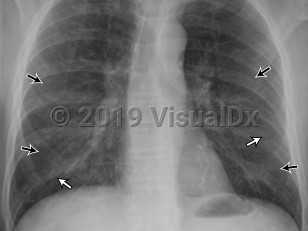

Extrinsic allergic alveolitis

Extrinsic allergic alveolitis manifests acutely with sudden-onset chest pain, cough, dyspnea, and fever following exposure to antigens. Headache, bibasilar crackles, inspiratory crackles, and malaise develop within 4-6 hours after exposure and may clear within 24 hours after removing the offending substance.

The subacute form manifests gradually and less severely and may recur infrequently. A chronic form, present in half of patients, is characterized by an insidious onset of cough, fatigue, progressive dyspnea, and weight loss. Tachypnea, respiratory distress, and clubbing portend a poor prognosis.